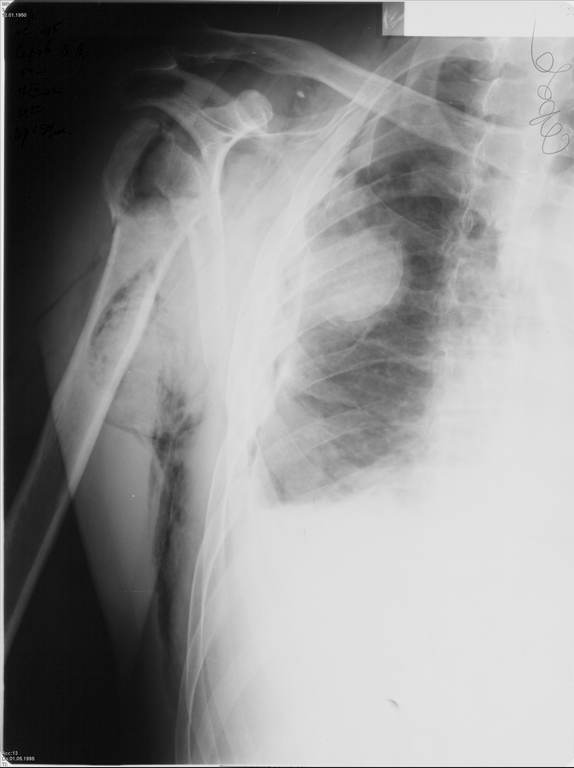

Я абсолютно согласен с Вами. Бугорки мы не выделяли и не фиксировали. Дело в том, что основная линия перелома проходит по анатомической шейке. И ниже нее кость повреждена, но существенного смещения осколков и бугорков до и во время операции не отмечено (прилагаю первичный снимок лучшего качества - рис. 1). Интраоперационно было установлено, что осколки находятся примерно на своих местах и плотно связаны с окружающими тканями. Мы не стали их выделять, мобилизировать и фиксировать, так как это все равно будет необходимо сделать при установке эндопротеза.

Александр, спасибо за столь высокую оценку. Нисколько не сомневаюсь, что и нам есть чему у Вас поучиться. Для иллюстрации прилагаю сегодняшний снимок с нашего обхода в шоковом зале реанимации (рис. 2).